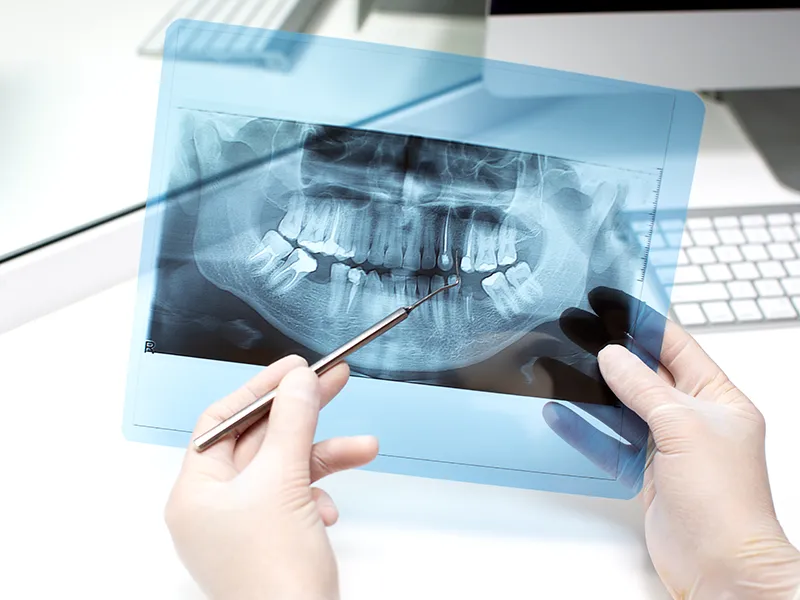

Panoramic X-ray

What is a dental panoramic X-ray?

A dental panoramic X-ray is a special image that can show the upper and lower jaws and the entire dentition at the same time. The image is taken in our office using the most modern method, so the image is made in digital form. The result gives our dentists a quick overview of the teeth and surrounding bones. It can also be an excellent help not only during screenings and treatments, but also in the search for foci.